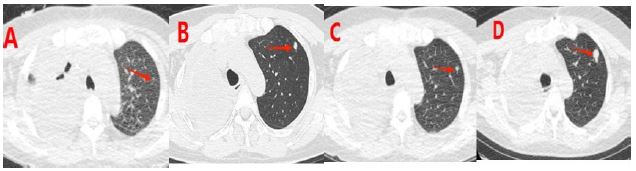

The patient gradually recovered after surgery and received three cycles of chemotherapy approximately one, two, and three months later. The specific dosages and schedules included: liposomal doxorubicin 60 mg on Day 1, dacarbazine 400 mg from Days 1 to 5, cyclophosphamide 100 mg on Day 1, and vincristine 1.6 mg on Day 1. After the third cycle of chemotherapy, the patient experienced a decrease in red blood cells and platelets. This indicated bone marrow suppression. Through active treatment and adequate rest, the patient gradually regained strength. Six months after surgery, the fourth cycle of chemotherapy was administered with an adjusted regimen of albumin-bound paclitaxel 150 mg on Days 1, 8, and 15. Additionally, radiotherapy was given to a gradually enlarging nodule in the left lung (Figure 3). The medical team subsequently administered targeted treatment using an anlotinib hydrochloride capsule. The patient was in good general condition and experienced no significant adverse reactions. Currently, the patient is stable, has an ECOG performance status of 1, and continues to receive oral targeted drug treatment.

Figure 3: (A-D) show chest CT images at 1 month, 2 months, 3 months, and 6 months after surgery, respectively. It can be seen that the nodule in the upper lobe of the left lung gradually increases.

This case highlights the importance of forming a rapid response team, including experts from radiology, vascular intervention, thoracic surgery, and molecular pathology, for managing pulmonary artery masses with fast-spreading pulmonary dissemination. Figure 3 illustrates that the multidisciplinary treatment approach reduced the time from diagnosis to surgery to just 12 days. This represents a 58% acceleration compared to traditional methods. This effective multidisciplinary model offers a novel clinical pathway to enhance the prognosis of these rare tumors.